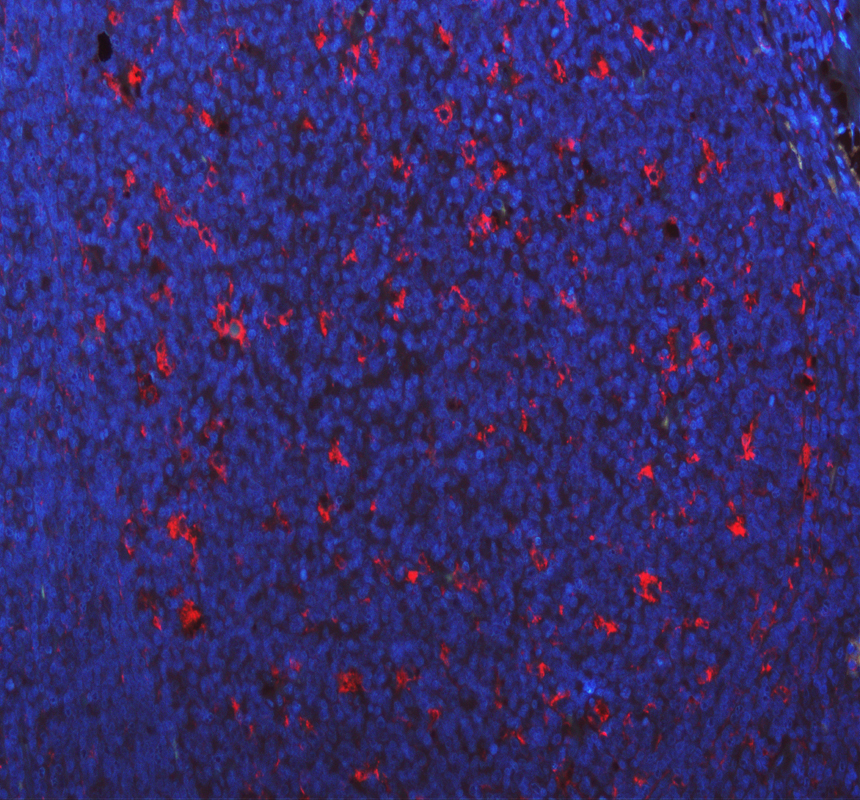

IF analysis of CD68 using anti-CD68 antibody (A00602-1).

CD68 was detected in a paraffin-embedded section of human tonsil tissue. The tissue section was incubated with rabbit anti-CD68 Antibody (A00602-1) at a dilution of 1:100. Fluoro488 Conjugated Goat Anti-Rabbit IgG (Green) (Catalog # BA1127) was used as secondary antibody. The section was counterstained with DAPI (Catalog # AR1176) (Blue).